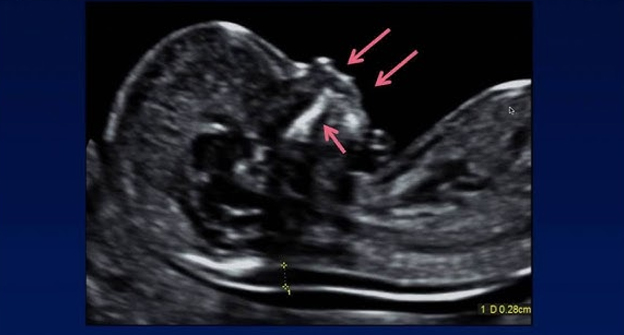

• Obstetric Ultrasound Techniques

• Fetal development stages and imaging

• Placental positioning and anomalies

• Diagnosing common fetal abnormalities